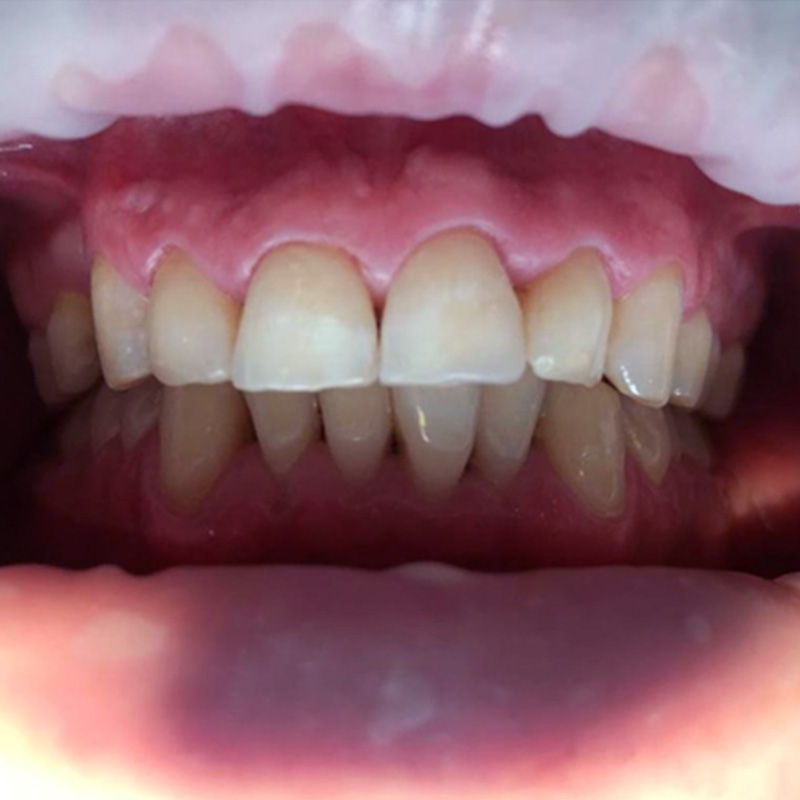

До и после лечения

У пациентки «Стоматологии Комфорта» были жалобы на кровоточивость дёсен во время чистки зубов. Также во время осмотра был обнаружен налёт на поверхности зубов. В результате поставлен диагноз: хронический генерализованный катаральный гингивит.

В процессе лечения были проведены мероприятия:

- проведена профессиональная гигиена полости рта;

- завершающая чистка зубов пастой Detatrine.